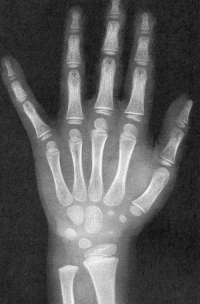

Sexo Masculino

2 anos

2 anos e 8 meses